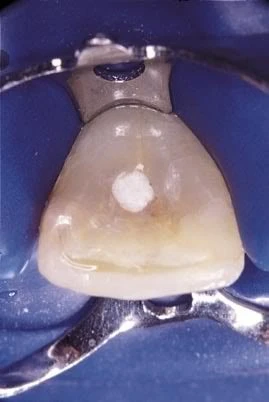

Lỗ mở tủy quá lớn hoặc đi nhầm hướng ống tủy

Do xác định sai cấu trúc giải phẫu của hệ thống ống tủy

NHỮNG SAI SÓT TRONG MỞ TỦY phán đoán sai ống tủy

trám bít kín khít ống tủy

Khắc phục: không có cách nào khác là chỉnh tìm lại đúng ống tủy, trám bít kín khít